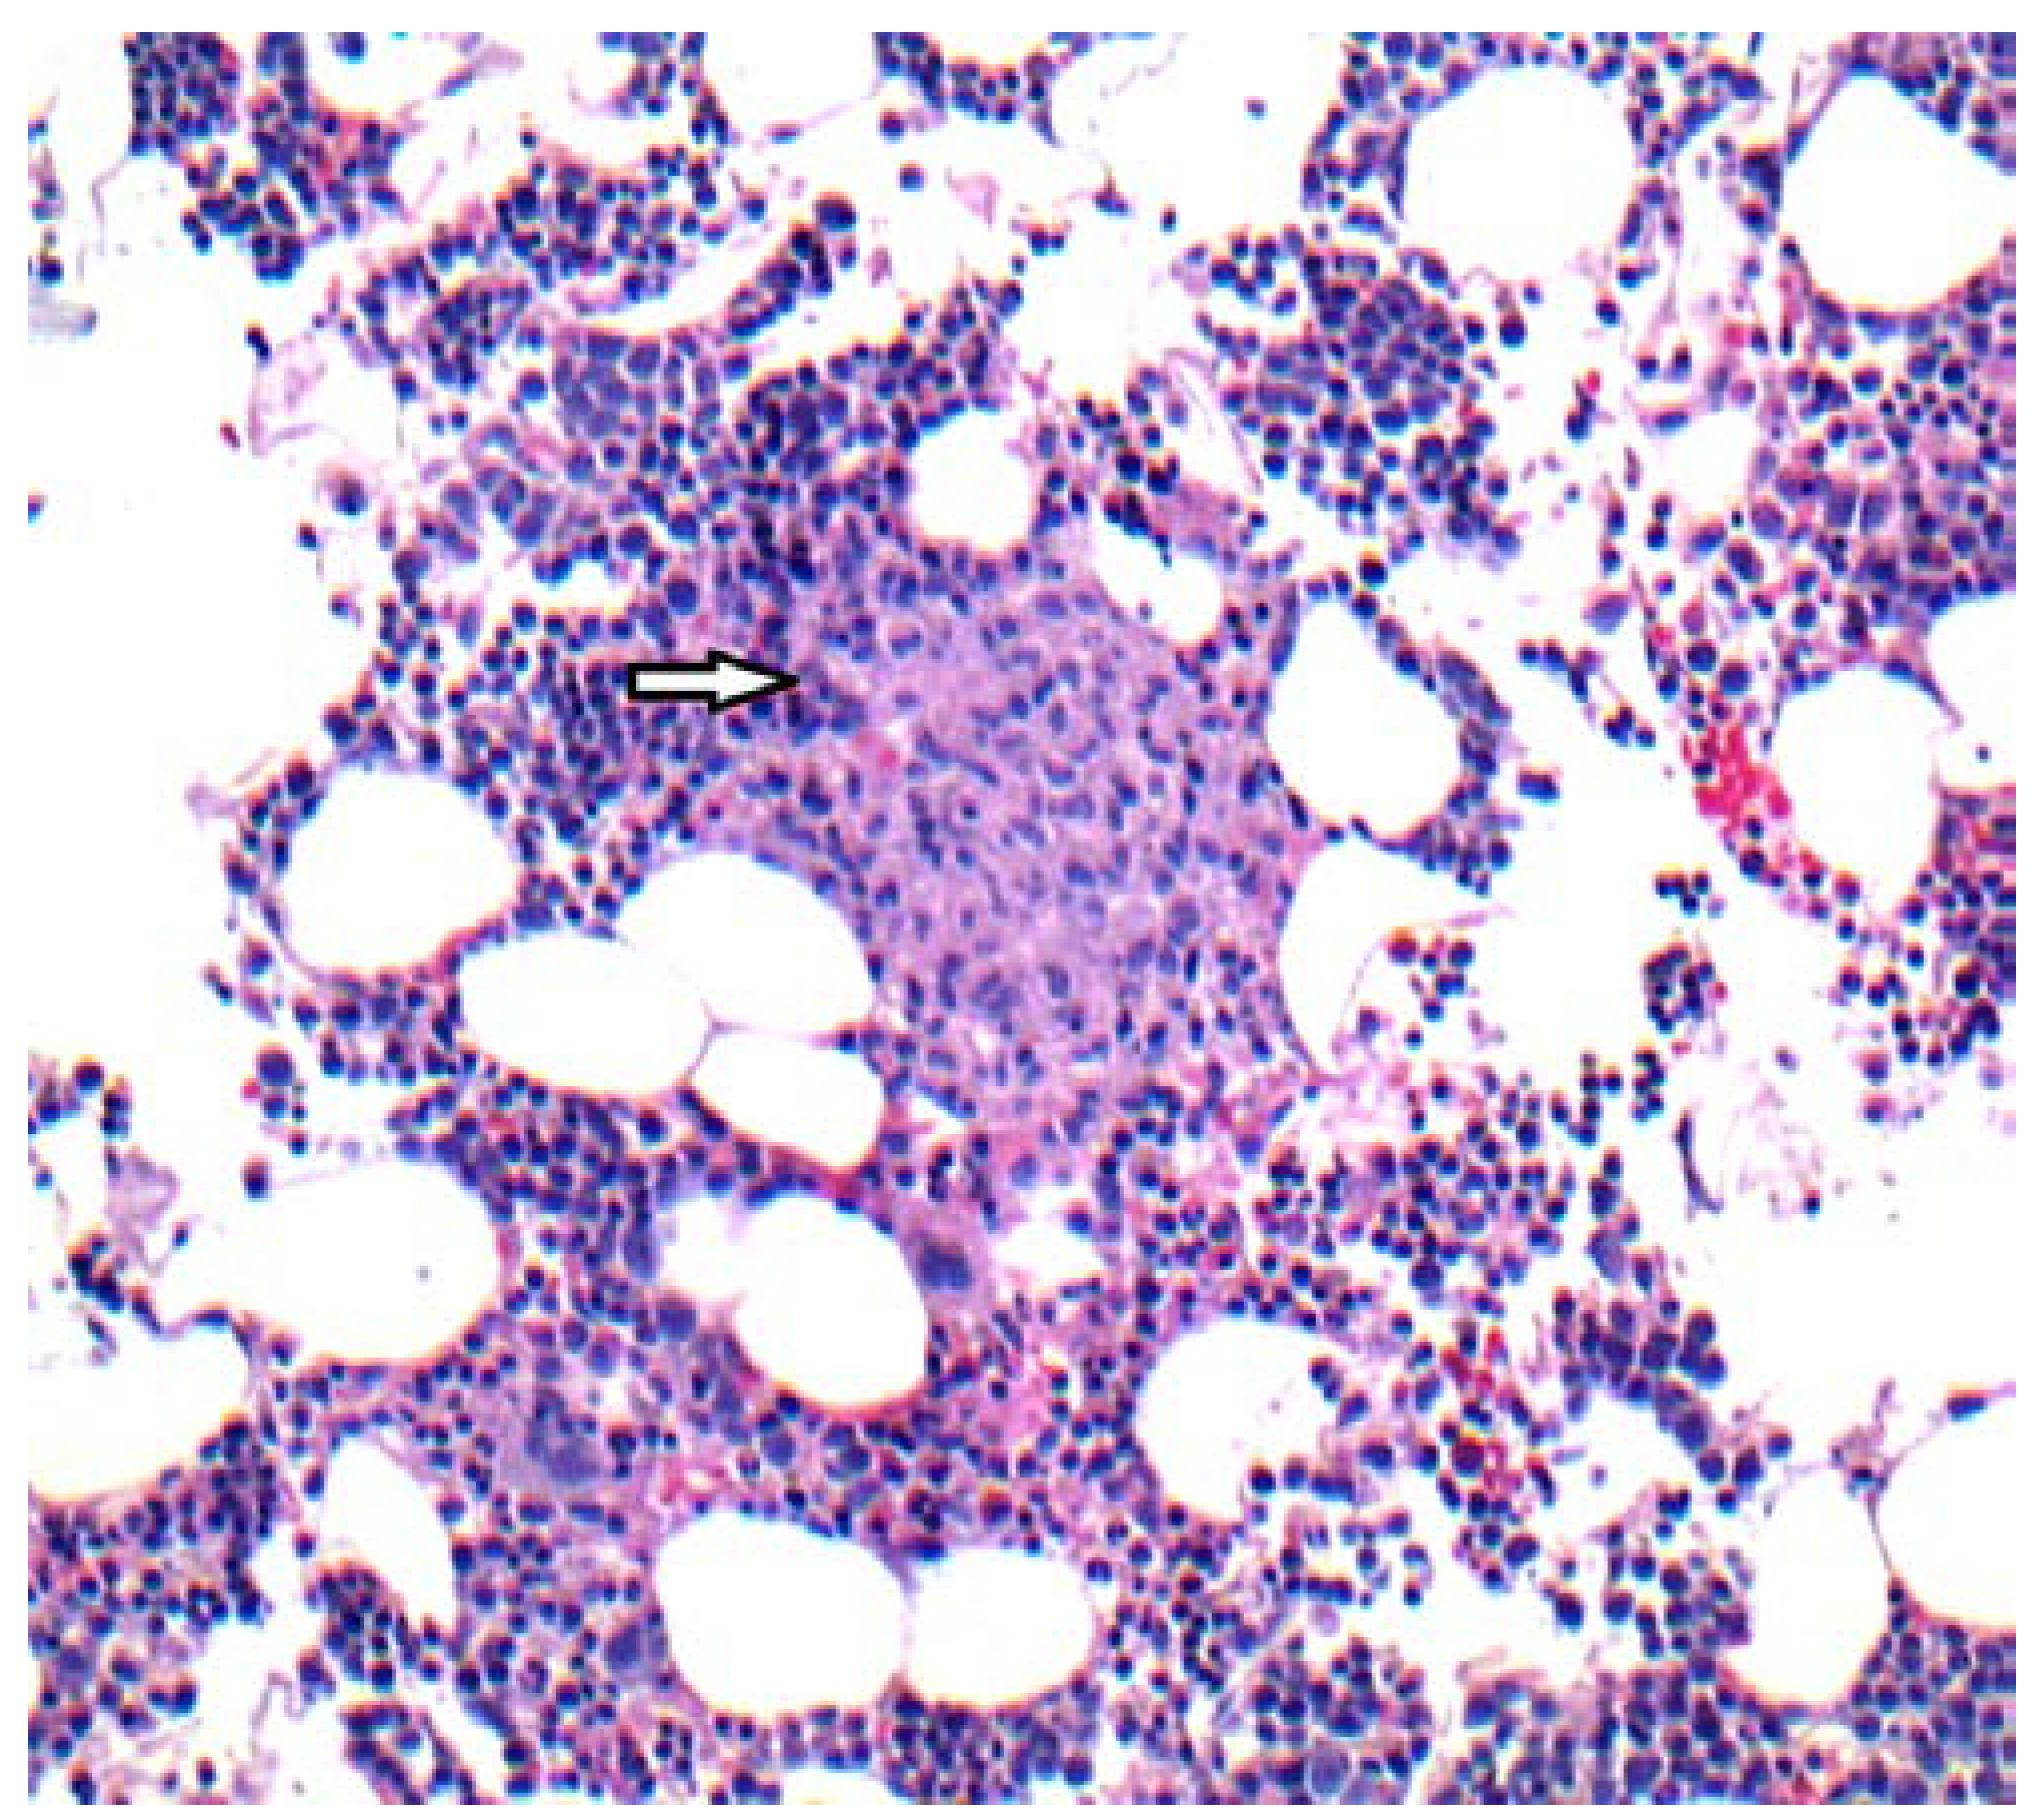

The patient was re-admitted one month later with complaints of sore throat, dry cough and fever after exposure to a sick contact. On examination, she was found to be febrile (temperature 39.3°C), and the spleen was mildly enlarged. Initial laboratory tests revealed total white blood cell count 0.7 K/µL, absolute neutrophil count 0.0 K/µL, platelet count 31 K/µL, serum creatinine 0.56 mg/dL, serum ALT 67 IU/L, serum alkaline phosphatase 118 IU/L. CT chest showed slight enlargement of multiple irregular pulmonary nodules previously described. Therapy was started with cefepime and oseltamivir. A bone marrow biopsy was repeated with flow cytometry analysis and cytogenetic studies. There was no evidence of relapsing ALL or HLH features, but new poorly-formed, non-caseating granulomas with negative GMS and AFB stains were seen (Figure 1).

Figure 1.

H&E stain, 10X. Bone marrow core biopsy demonstrating a poorly formed, light pink colored non-caseating granuloma (arrow) surrounded by normal hematopoietic cells.